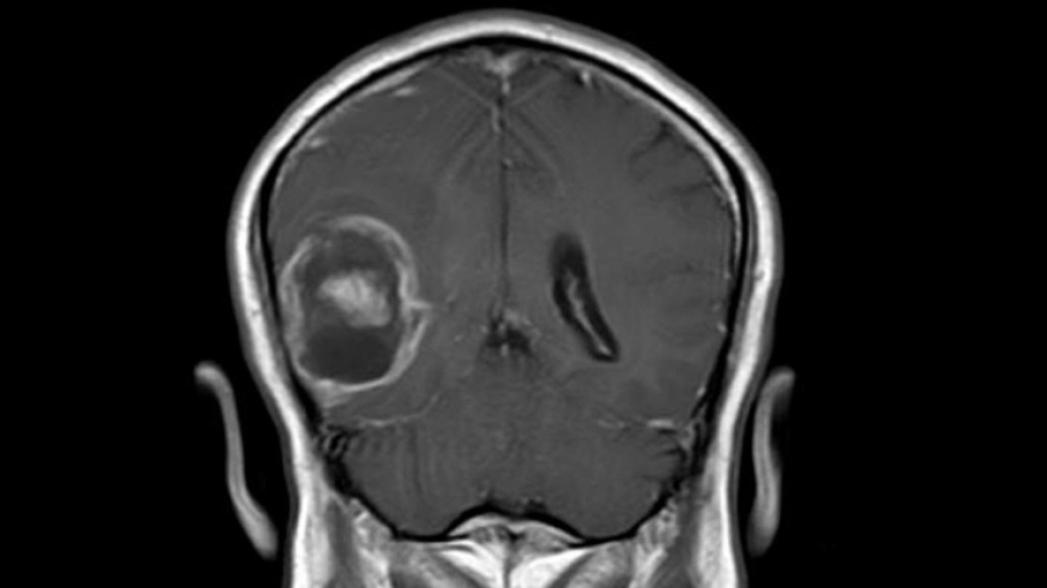

Решение IBM Watson for Genomics анализирует генетические данные опухоли мозга, объединяя их с данными научных работ в этой сфере, и выдает свои выводы относительно лечения. Причем делает оно это всего лишь за небольшую долю времени, требующуюся для профессиональных экспертов в этой сфере. Такие данные были получены недавно при исследовании проверки концепции и эффективности использования этой системы для диагностики рака, результаты которого были опубликованы в Neurology: Genetics.

* Мультиформная глиобластома - это наиболее частая и наиболее агрессивная форма опухоли мозга, которая составляет до 52 % первичных опухолей мозга и до 20 % всех внутричерепных опухолей.